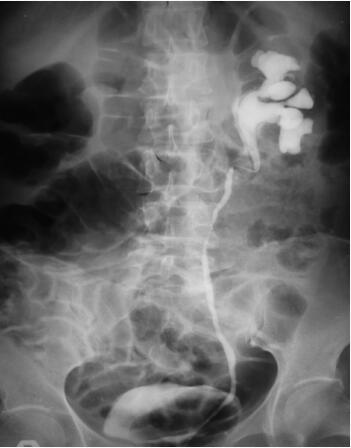

肾盂输尿管逆行造影(图45-1):左侧肾盂积水,近段输尿管向中线移位。

图45-1 左侧肾盂积水,近段输尿管向中线移位

(1)典型IVP可见不同程度的肾盂积水,显示近段输尿管向中线移位,远端输尿管逐渐变细,多数为双侧。这是认为具有诊断意义的检查,可有几个特征性改变:①不同程度的肾盂、输尿管积水伴输尿管扭曲扩张;②输尿管向脊柱方向移位;③有外源性输尿管压迫症,管壁光滑。

2. 若患者肾功能明显降低可行逆行造影,表现与IVP类似。